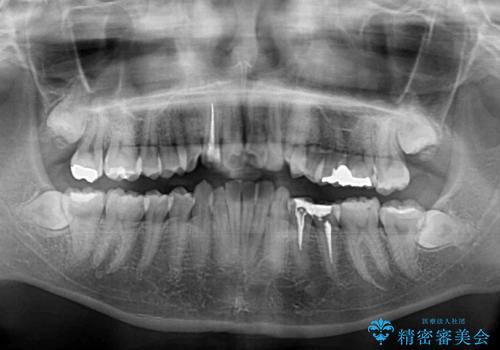

- 虫歯が多く、磨きにくい歯並びを改善したいとのことで来院された患者様です。

歯列は叢生が認められる程度でしたが、やや前突感があったので、少しでも口が閉じやすくなるように仕上げる方針としました。

神経を取り除かれている歯3本以外にも虫歯が認められたため、事前に処置を行い、インビザラインにて矯正治療を行うこととしました。

神経が取り除かれている歯は、クラウンによる補綴治療が必要であるため、矯正治療後にオールセラミッククラウンにて補綴治療を行うこととしました。